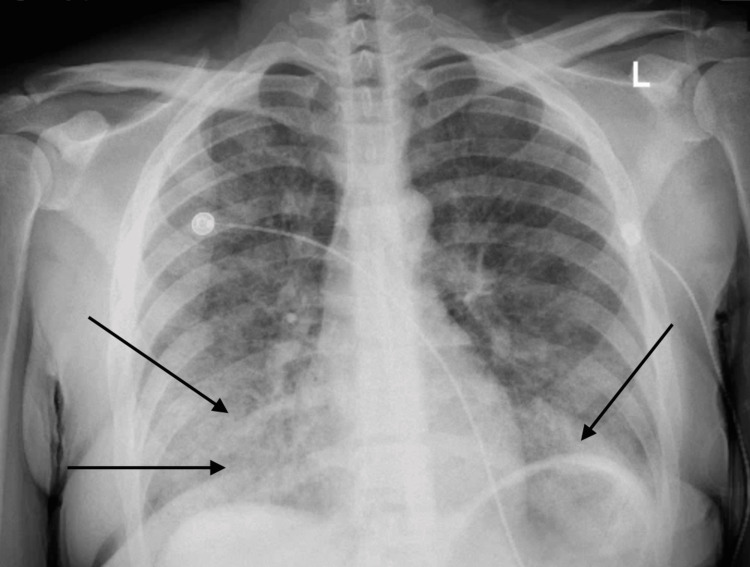

On initial evaluation, the patient was alert and oriented but noted to be hypoxic with oxygen saturation of 91% on room air and required supplemental oxygen. Chest X-ray initially revealed bilateral patchy opacities (Figure 1), and contrast-enhanced computed tomography (CT) of the chest revealed diffuse ground-glass opacities (GGOs) (Figure 2). Laboratory tests showed an initial hemoglobin level of 13.3 g/dL, which precipitously dropped to 9.3 g/dL (reference range: 12.0-16.0 g/dL) within 24 hours. Urine toxicology was positive for cannabis, while renal function and coagulation studies were unremarkable.

Typical pulmonary radiological findings of DAH include diffuse bilateral alveolar infiltrates, which are often described as GGOs on chest CT scans or consolidations on chest X-rays. However, in the early stages, chest X-rays can fail to capture the full extent of the disease, and serial X-rays or chest CT should be considered for a prompt and accurate diagnosis. The infiltrates observed in DAH are typically patchy or confluent and can progress rapidly, reflecting the alveolar spaces filling with blood. This pattern is usually non-segmental and predominantly affects the dependent lung regions [ref. 10].

Chest CT is more sensitive than chest X-rays in detecting the features of DAH. GGOs, as seen on CT scans, are more prominent and provide a clearer delineation of the extent of alveolar hemorrhage compared to consolidations. Unlike infectious pneumonia, the infiltrates in DAH generally lack air bronchograms, which can aid in distinguishing between these conditions. In the acute setting, chest imaging may appear normal in up to 50% of cases, which highlights that normal radiological findings do not rule out the diagnosis. Rapid imaging assessment combined with clinical evaluation is crucial for timely identification and intervention in cases of DAH [ref. 11].